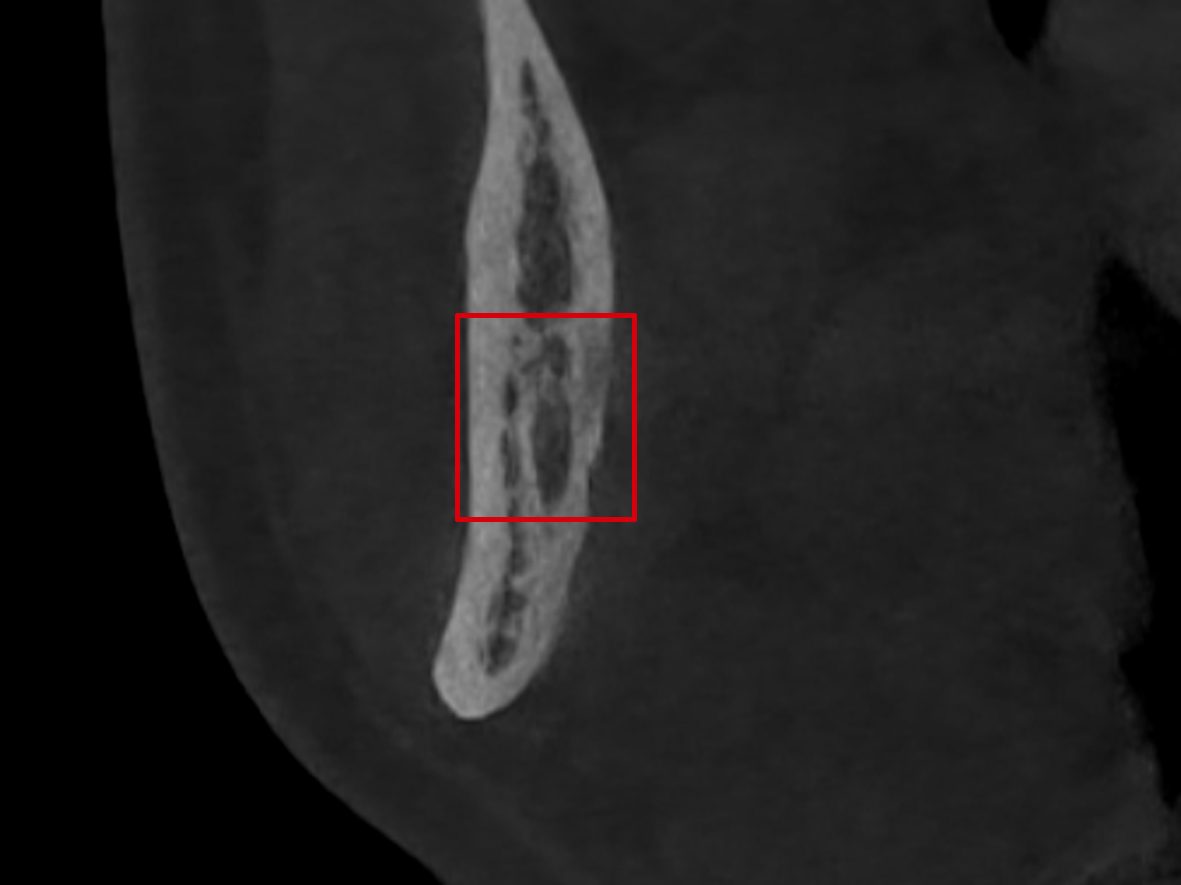

下颌牙回袢